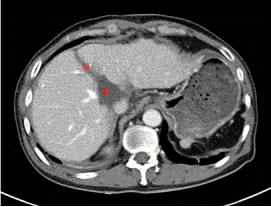

通過CT、磁共振以及三維重建的圖像來看,王先生的腫瘤位于肝臟尾狀葉,除左側(cè)可見少量肝組織以外,腫瘤已侵犯絕大部分的尾狀葉!“跟土豆差不多大!”胡偉表示,王先生的肝臟腫瘤約有5*5*4㎝大小,手術(shù)切除對于他來說是目前唯一有效的治療方案!

術(shù)前增強CT顯示腫瘤位于肝臟尾狀葉